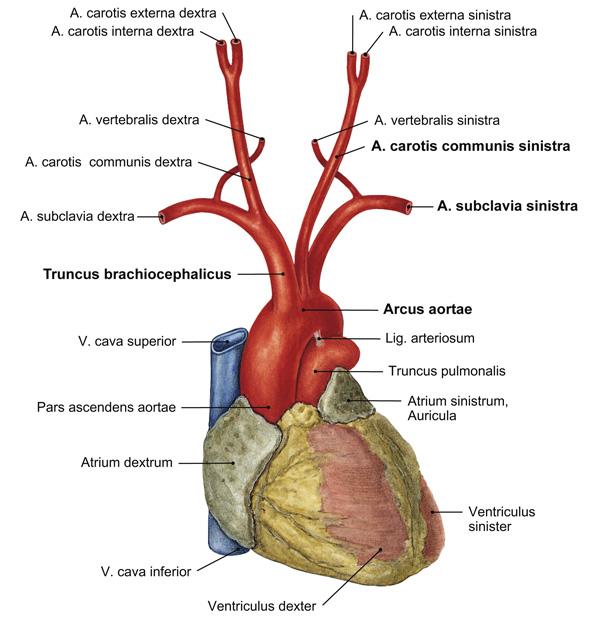

Fig 3.04: Arcus aortae

omslagplooi pericardium trachea esophagus tr. pulmonalis lig. arteriosum isthmus aortae (vernauwing lumen t.h.v. lig. arteriosum) linker n vagus (X) -

linker n vagus > linker n laryngeus recurrens = n recurrens

zijtakken arcus aorta

-

tr. brachiocephalicus

a subclavia dextra a carotis communis dextra

a carotis communis sinistra a subclavia sinistra (a thyroidea ima)